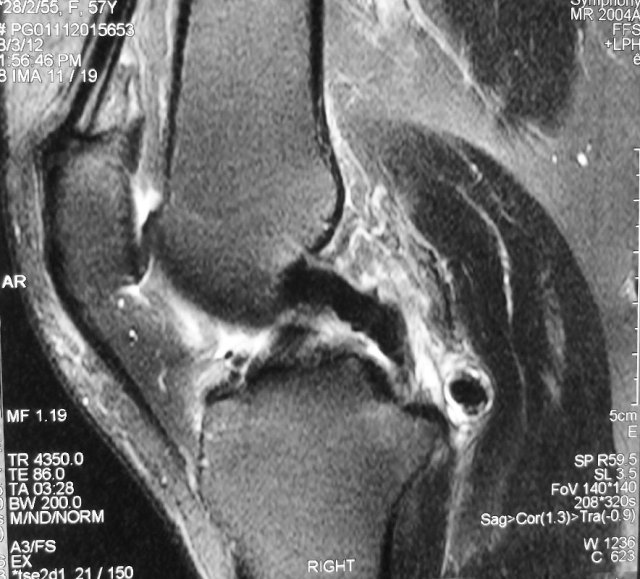

This is a 60 year old woman who presented with acute pain and swelling of her right knee. There was no prior injury or trauma to her right knee. She described having locking sensations of her knee followed by pain and swelling.

MRI showed a large loose body in the back of her knee joint.